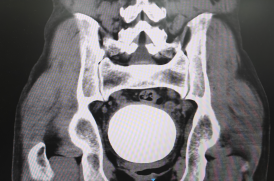

“从没见过这么大的膀胱结石!” 近日,广元市第一人民医院泌尿外科联合多学科团队,成功为一位聋哑患者实施手术治疗,取出一枚直径约9cmx9cm,形态惊人的巨大膀胱结石。其大小与成年男性拳头几乎无异,堪比一颗饱满的“小苹果”,让在场医护人员无不感到震惊。这一高难度手术的成功开展,解除了患者的长期病痛,彰显了医院在处理复杂泌尿系结石及服务特殊群体方面的过硬实力与深厚仁心。

该患者59岁男性,入院时,患者聋哑独居,被其邻居发现食欲不佳,精神差,卧床不起,小便失禁,后被送入广元市第一人民医院急诊科就诊,因双肾积水,收治泌尿外科。影像学检查显示,患者膀胱内竟藏有一颗直径约9cm的巨大结石。如此巨大的结石在临床中十分罕见,长期存在体内不仅给患者生理上带来了极大痛苦,还严重影响生活质量。

精准高效实施:在麻醉科团队的精心保障下,范地兵副主任带领手术团队,凭借丰富的经验和娴熟的技巧,成功克服空间限制,严密保护膀胱周围组织,完整取出这颗沉甸甸,重达590g的巨大结石。